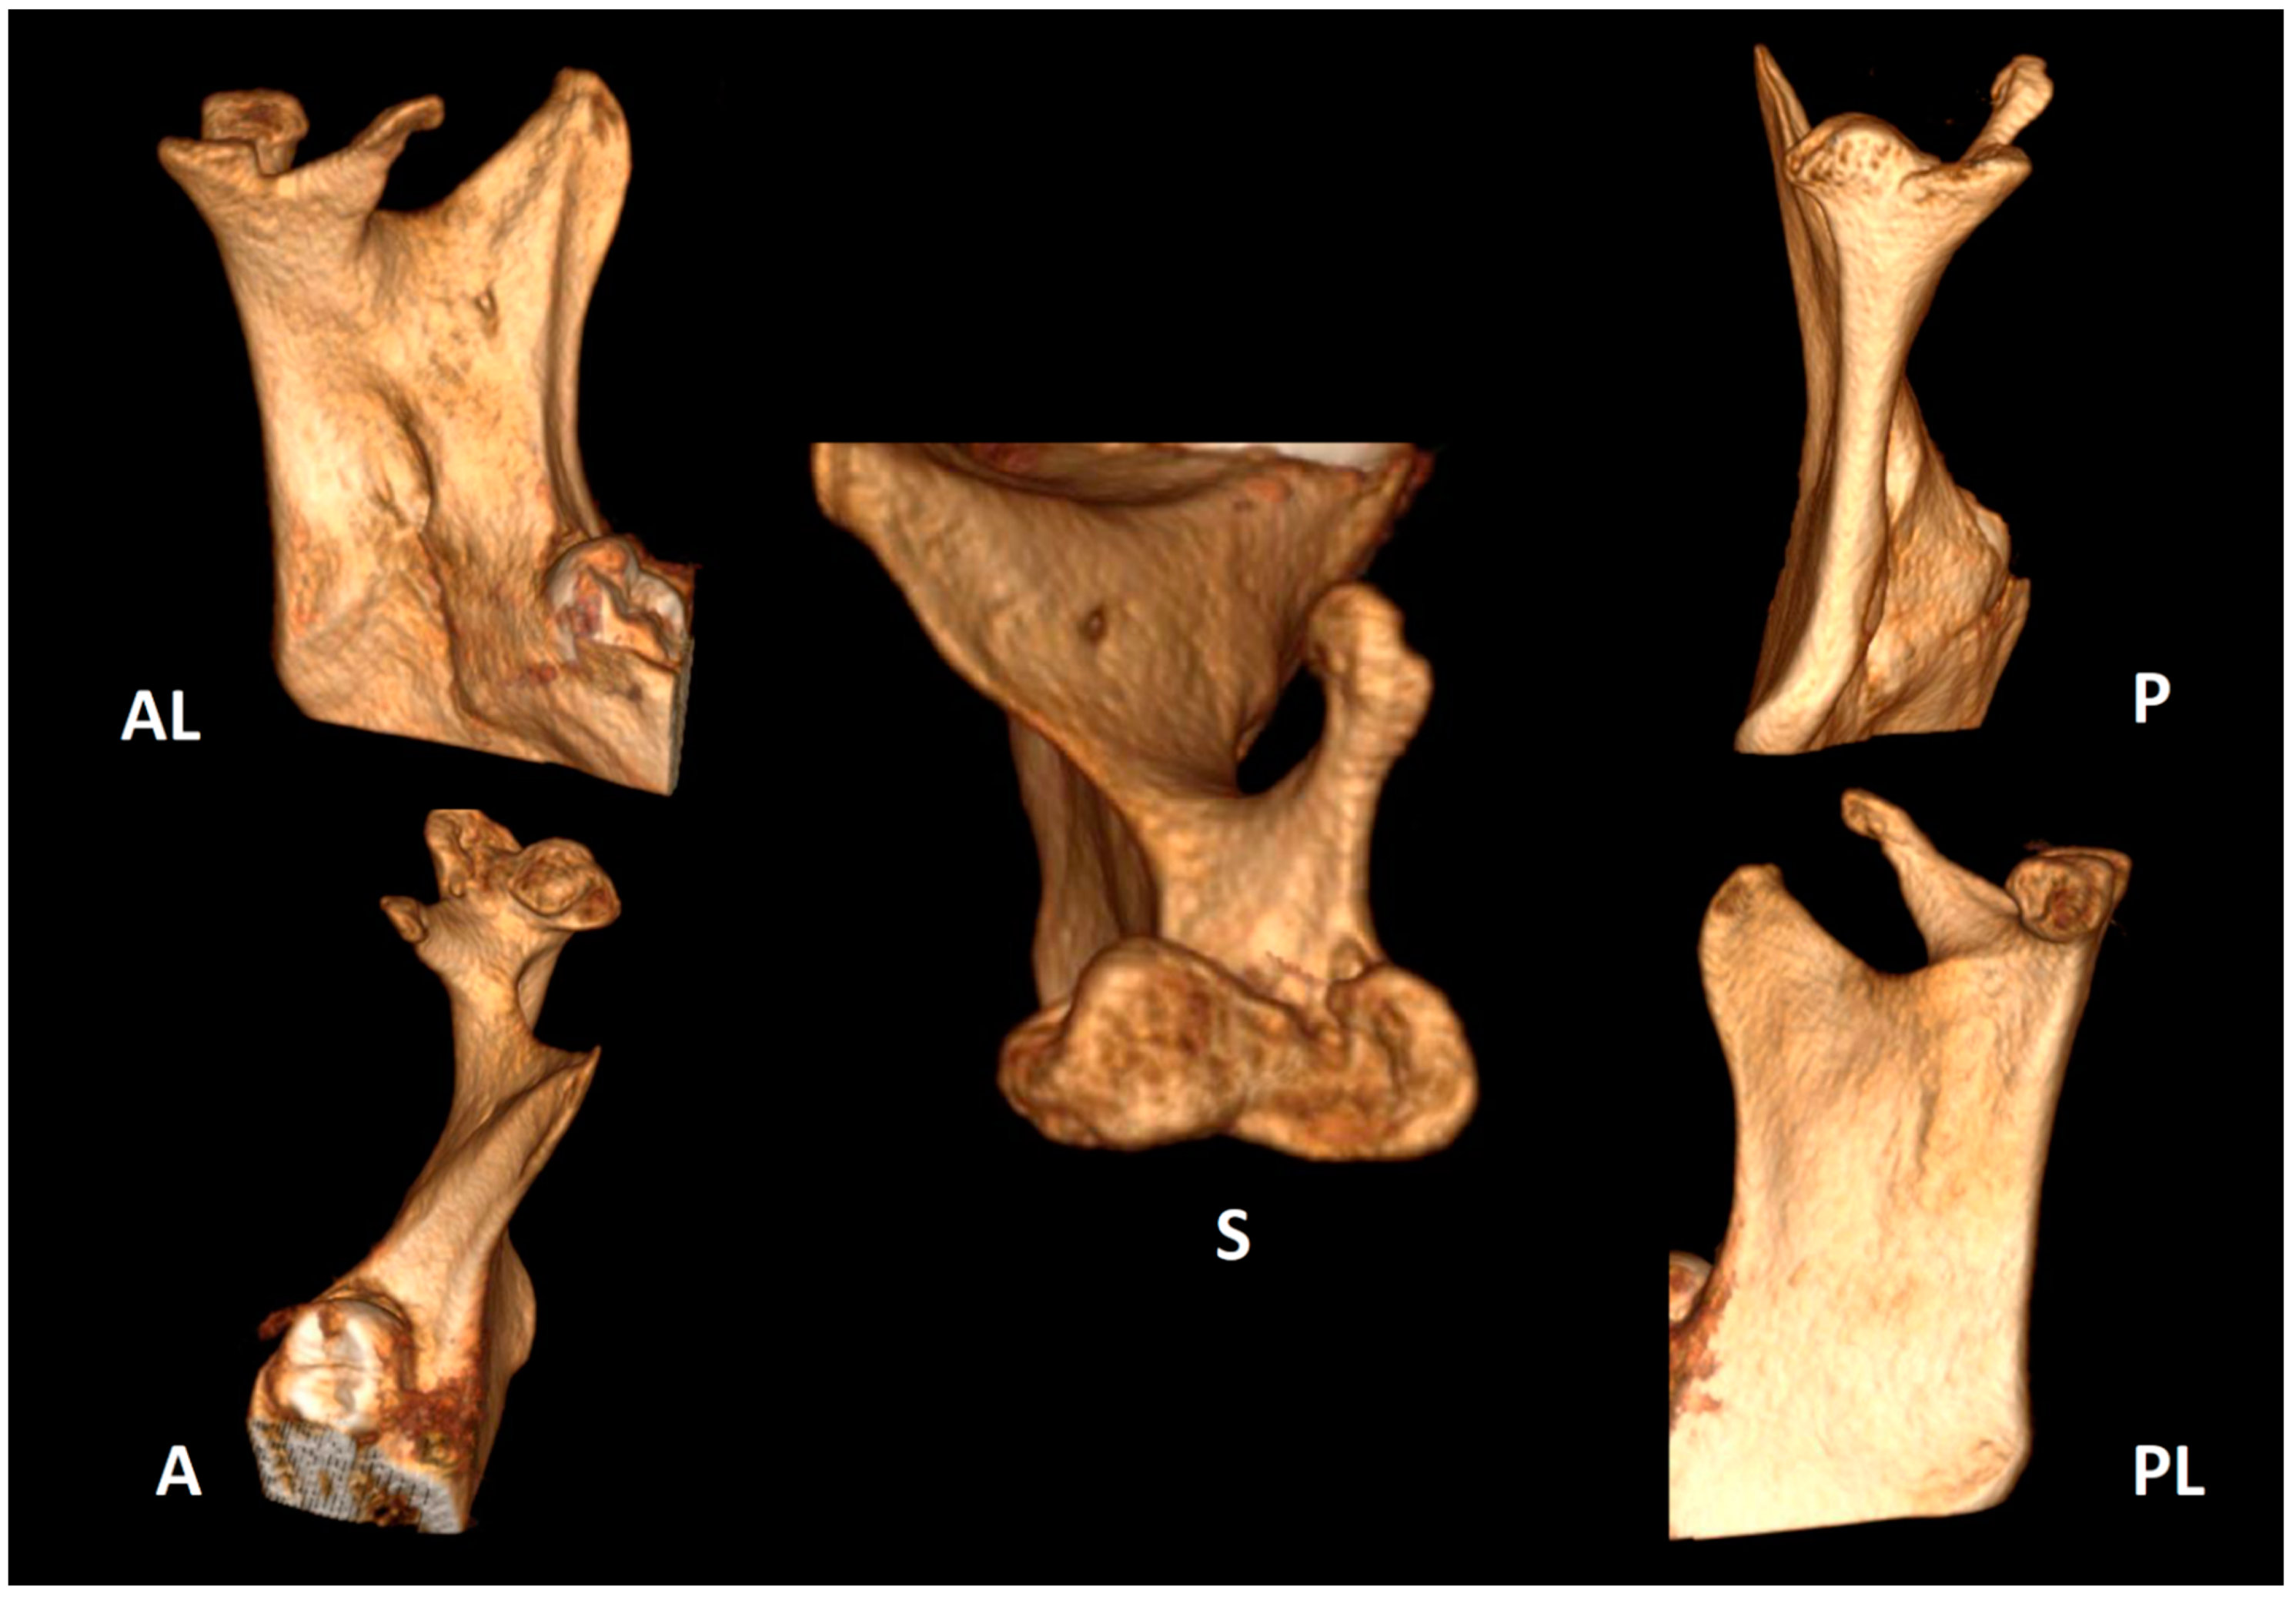

| Sezgin & Katipman 2009 [3] | M, 31 | Mandible deviated to the right | Trauma | FU | - |

| Prasanna T. et al., 2015 [1] | F, 26 | Mild facial asymmetry, micrognathia & deviation of the mandible to left | - | None | - |

| Hernández-Andara A. et al., 2017 [8] | M, 12 | Facial asymmetry & a clicking noise in the left TMJ | Trauma | FU | - |